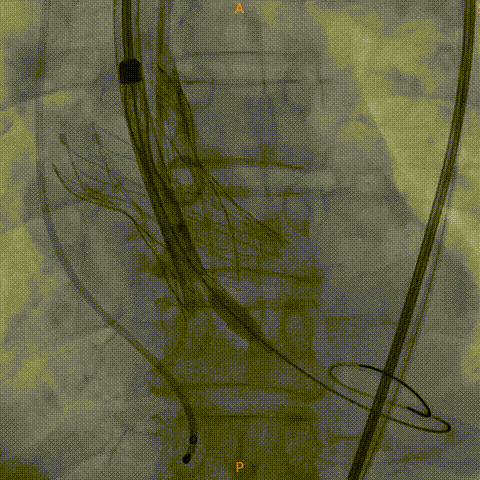

瓣膜膨胀不良进行球囊后扩

造影显示有瓣周漏

植入瓣中瓣

瓣中瓣形态良好,无反流